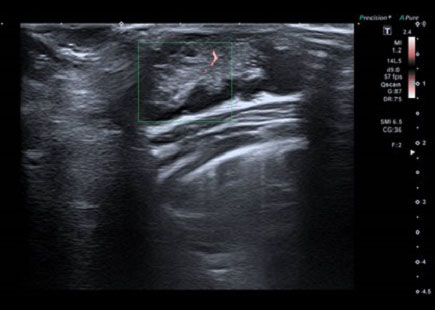

Para realizar el diagnóstico diferencial entre estas entidades clínicas, la ecografía resulta de gran utilidad. El tejido mamario en la intumescencia mamaria neonatal es relativamente hipoecoico, mientras que el aumento en la ecogenicidad es característica de la mastitis. El absceso por su parte será anecoico o ecoico dependiendo de la naturaleza de su contenido. Estos dos últimos presentarán un aumento del flujo en el tejido graso periférico en el Doppler color, pero el flujo en el absceso estará ausente a diferencia de la mastitis debido a la hipervascularización interna4,5 (Figs. 3, 4 y 5).

| Figura 5. Ecografía: quiste mamario izquierdo de 7 mm, anecoico, que protruye sobre superficie cutánea, sin aumento de la vascularización periférica |